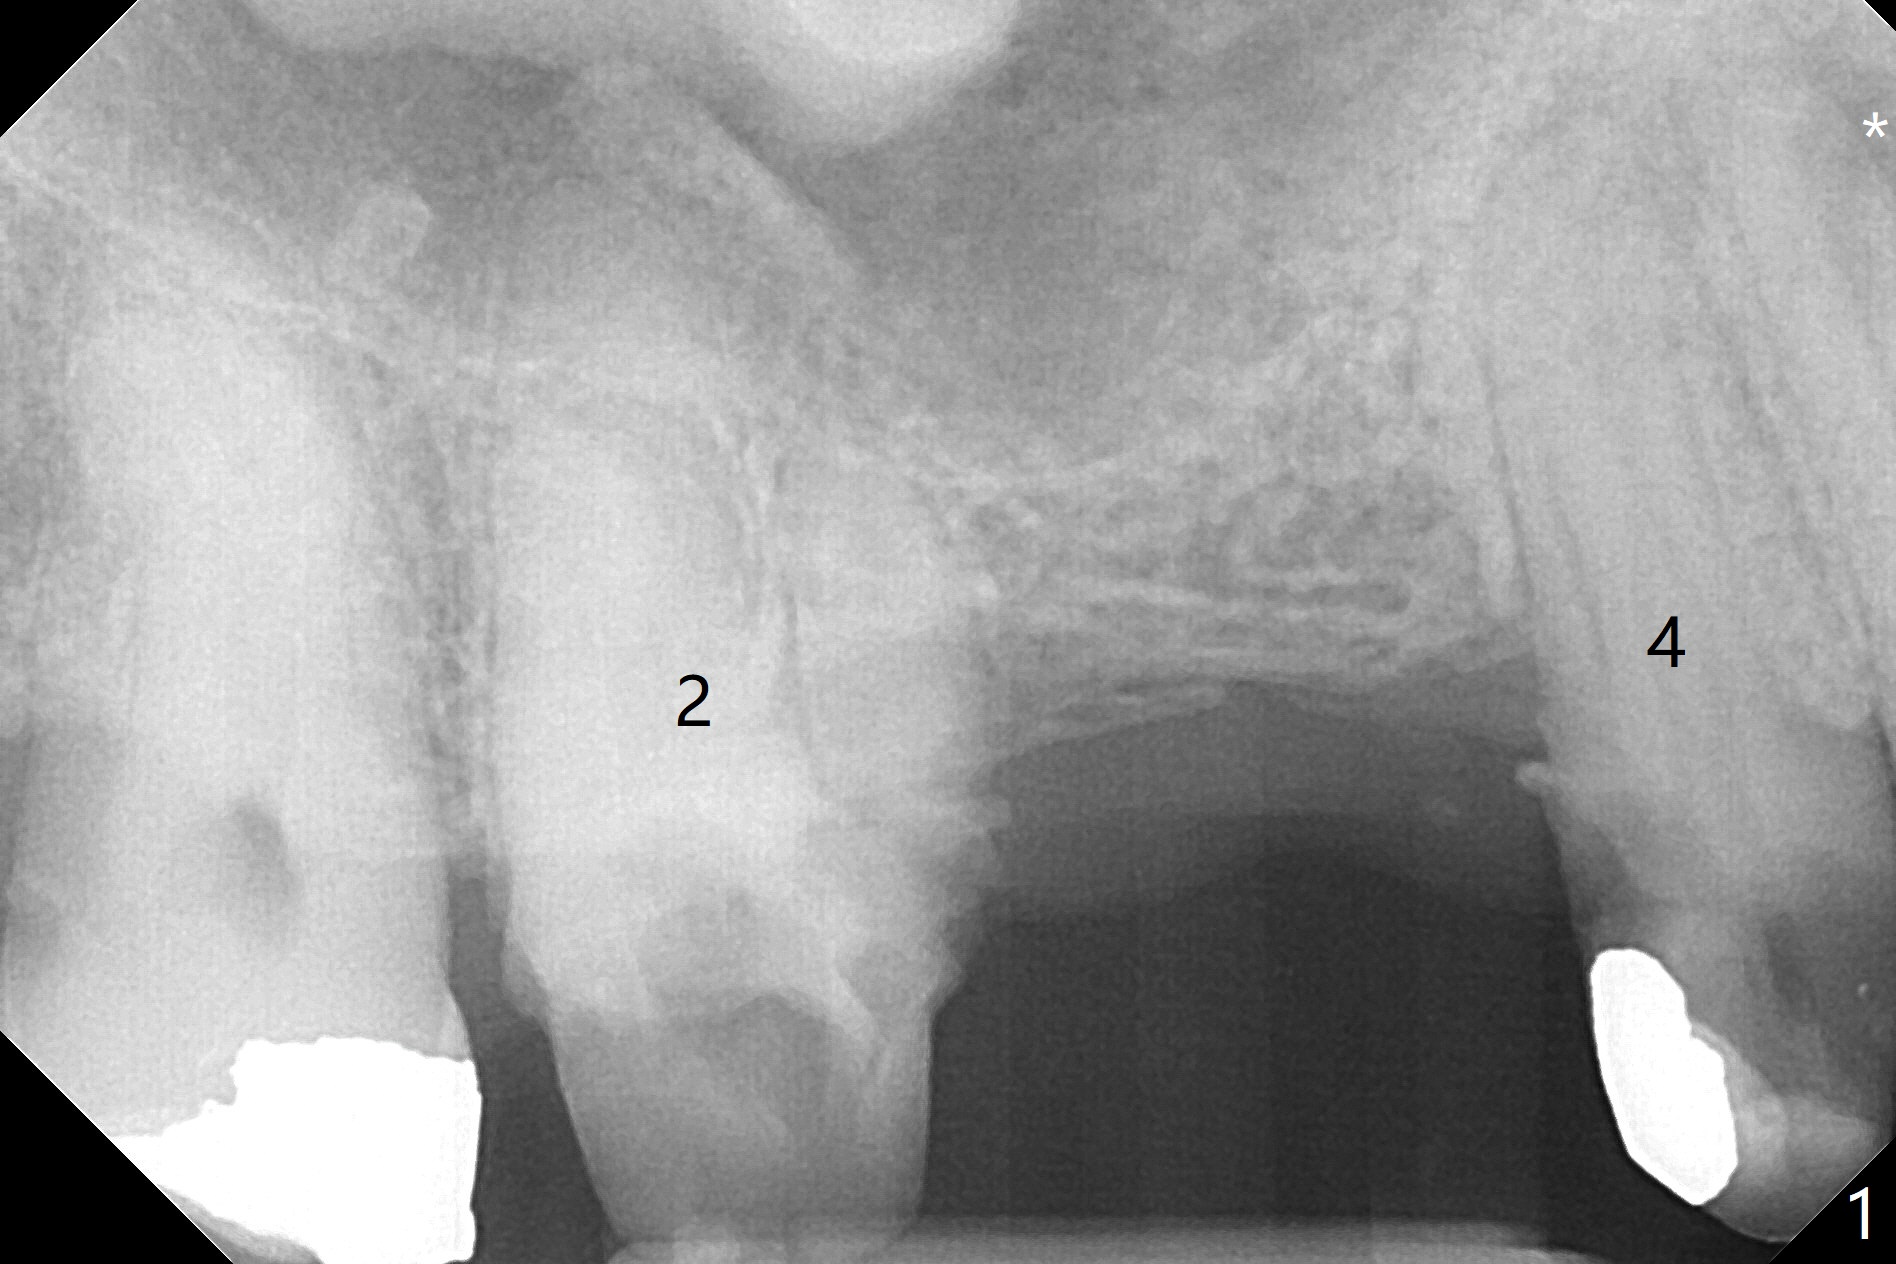

A 64-year-old man requests implant restoration after the upper FPD dislodges (Fig.1). The measurement of the septal height at #2 by PA (Fig.2) is not as precise as CBCT (Fig.11, taken 4 years earlier). There appears to be 2.8 mm bone apical to the tooth #4 (Fig.2); in contrast, the bone is more or less buccal and palatal to the root apex shown by CT (Fig.5). Furthermore CT more clearly shows apical lesions of the tooth #5 (Fig.3,4) than PA (Fig.2). In addition to pulpal test, RCT should be done for #5 prior to implant placement at #4.